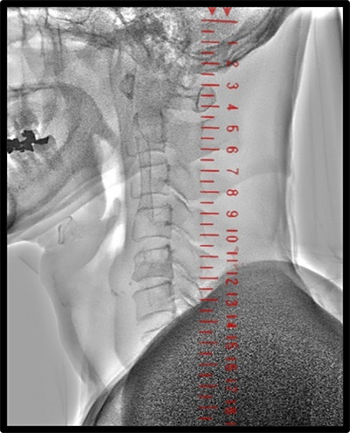

Cアームの角度を変えた場合、寝台上に置く必要がある実物のスケールは視野外となってしまう。しかし、バーチャルスケールは自由な角度と位置に配置可能で、どのような角度でも位置情報として使用できる。これはCASの様な側面の透視が重要となる手技において特に有効である。図9にCASでの臨床使用例を示す。総頚動脈から内頚動脈にかけて正面と側面で位置合わせをする事で、前述したように拡大率が一致し、バルーンサイズ選択やステント留置にも有益な情報となる。QVAで必要となるキャリブレーションに利用すれば、視野内に造影カテーテルが写っていなくても精度の高いキャリブレーションが可能となる。

IGS630_Fukaya_12.jpg

図9 CAS